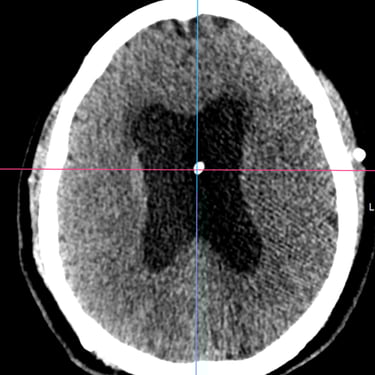

Hidrocefalia y Disfunción de Derivación: Colocación de Derivación Ventrículo-Pleural

La hidrocefalia puede complicarse cuando la derivación ventrículo-peritoneal deja de funcionar correctamente, produciendo aumento de la presión intracraneal y síntomas como cefalea, vómitos, somnolencia o deterioro neurológico. Cuando el peritoneo deja de ser una opción viable debido a infecciones, cirugías previas o mala absorción, se considera la derivación ventrículo-pleural como alternativa efectiva. Este procedimiento permite redirigir el líquido cefalorraquídeo hacia la cavidad pleural, donde puede ser absorbido adecuadamente. La intervención oportuna restablece el drenaje del LCR, reduce la presión intracraneal y mejora el pronóstico del paciente, siendo una solución segura en casos de disfunción peritoneal.